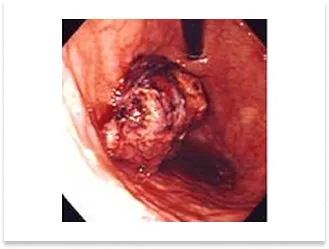

直腸S状結腸移行部の進行癌症例

術前内視鏡写真